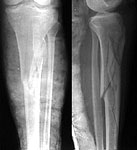

I amseeking advice management of young male motorcyclist who has sustained highenergy direct impact to his right shin resulting in closed highly comminutedfracture of his right tibia.(See attached xray). He also has fracture of his rtlateral malleolus not shown on attached xray. Is interlocking nailing an optionor it has to treated conservatively ?

This is a difficult fracture. I would reduce and fix the tubercle (minimalopen vs percutaneously) and put the patient in an Ilizarov. The fracture is tooproximal for a nail.

I think IM nailing of this fracture is not very easy, you have a highcomplication rate even with a very experienced surgeon we would treat thisfracture with a plate ( as long as soft tissues allow us to do so) perferably apercutaneous plate or a LISS plate with angle stable screws.

A nail would need additional blocking screws to improve the stability , and itmay be wise to start with two srews in the proximal tibia to be sure that thesplit is not dislocated during the nailing.

Ace or new Richards nail with a small Herzogs curve will fit this nicely, butthe starting point will have to be just distal to the meniscal edge, just likeDean Cole shows. Heck, dean fixes Tibial plateau fractures with nails. You mayhave to hang the leg from a distal femoral traction pin and a hook in the ceilingto hyperflex, but it works well and the patient would be able to walkimmediately. A hybrid will cause the knee to get infected as the pins will haveto be too high and result in a pin tract infection within the joint capsule.

From: Kevin Pugh

This fracture has a split that goes up into the joint on the lateral view thatwould displace upon nailing. The technique described is probably possible, butextremely demanding. For the rest of the world that isn't the distinguished Dr.Sanders or Dr. Cole, I think a non-medullary solution is the way to go. Platingis an option as long as the medial side is handled in a biologically friendlymanner. A hybrid frame would probably not provide the stability you need over thelong metaphyseal/diaphyseal segment. A full circular frame would be more stable.If the proximal end is stabilized with screws, the wires will not need to be inthe knee capsule.